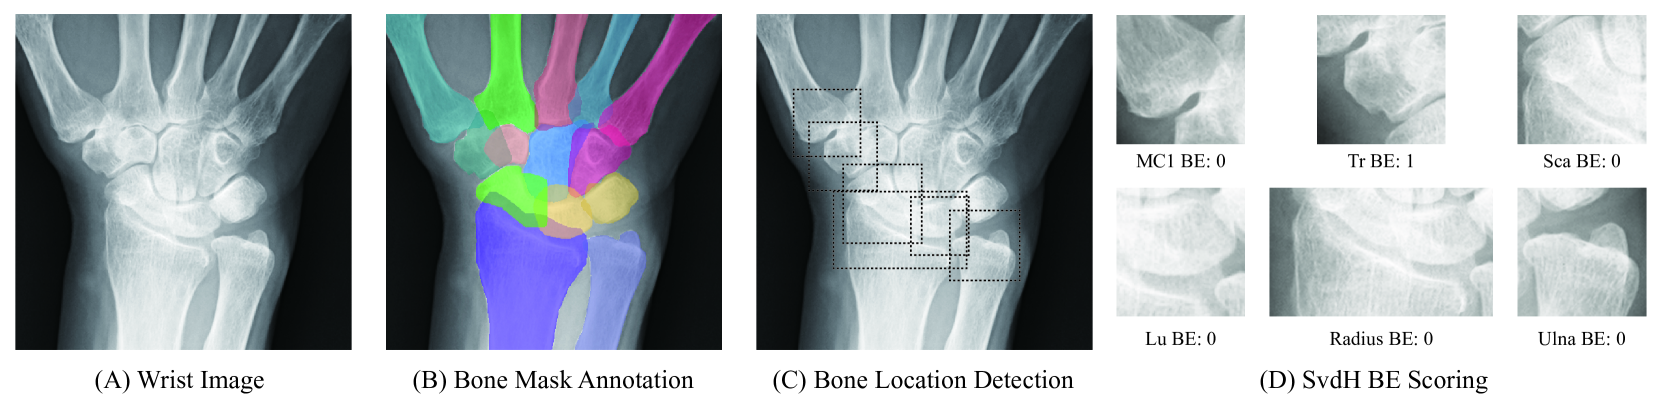

Refer to caption

Figure 1: Overview of the RAM-W600 dataset, designed for wrist bone segmentation and SvdH BE scoring tasks. (MC 1 to 5: Metacarpal 1 to 5; Tz: Trapezoid; Tr: Trapezium; Sca: Scaphoid; Radius: DistalRadius; Cap: Capitate; Ham: Hamate; Lu: Lunate; Tri: Pisiform &\&& Triquetrum; Ulna: DistalUlna)

Figure 2: Distribution and Statistics for the age, gender, institution, number of shots, and BE scores in the RAM-W600 dataset. (A) Circular overview of the internal cohorts. Each bar around the circular plot represents a unique patient. The concentric layers from inner to outer encode: (i) Gender distribution. (ii) Institution distribution. (iii) SvdH BE scores in both wrists for each study. Patients with multiple studies are represented multiple times in this layer. (iv) The phase of imaging and the patient’s age at the time of each acquisition. (B) Circular overview of the external validation data. Similar to (A), each bar around the circular plot represents a unique patient. (C) Distribution of SvdH BE scores by joint surface.

Figure 6: Wrist bone segmentation.(A) Original wrist radiograph. (B) Predicted instance segmentation masks. (C) Ground truth annotations. The right panel reports the segmentation performance per bone.

In this task, we annotate 14 distinct wrist bones, including both carpal, metacarpal components and Radius &\&& Ulna. Notably, the pisiform and triquetrum bones are difficult to distinguish in clinical practice due to their overlapping appearance and low visibility on standard radiographs. Consequently, it is challenging to evaluate them as independent diagnostic regions [45]. Therefore, we merge these two structures into a single category during annotation to reflect their practical indistinguishability. The input to the segmentation model is the wrist ROI cropped from the radiograph, and the output and ground truth are a pixel-wise mask for each annotated bone, as illustrated in Fig. 7.

Figure 7: Image input and annotation.(A) Raw wrist radiograph. (B) Instance bone segmentation mask annotation (C) bone location annotations for target regions. (D) SvdH BE scores assigned to each joint region.